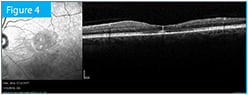

The patient is a 45-year-old otherwise healthy male who presented with sudden loss of vision in his left eye. Visual acuity OS was counting fingers inferiorly at 6 feet. Clinical exam and color fundus photography (Figure 1) revealed a hemiretinal vein occlusion, which fluorescein angiography confirmed (Figure 2). Central retinal thickness was 624 µm as measured by Spectralis SD-OCT (Heidelberg Engineering) (Figure 3).

Figure 3. At the patient’s initial visit, central retinal thickness was 624 µm as measured by Spectralis SD-OCT.